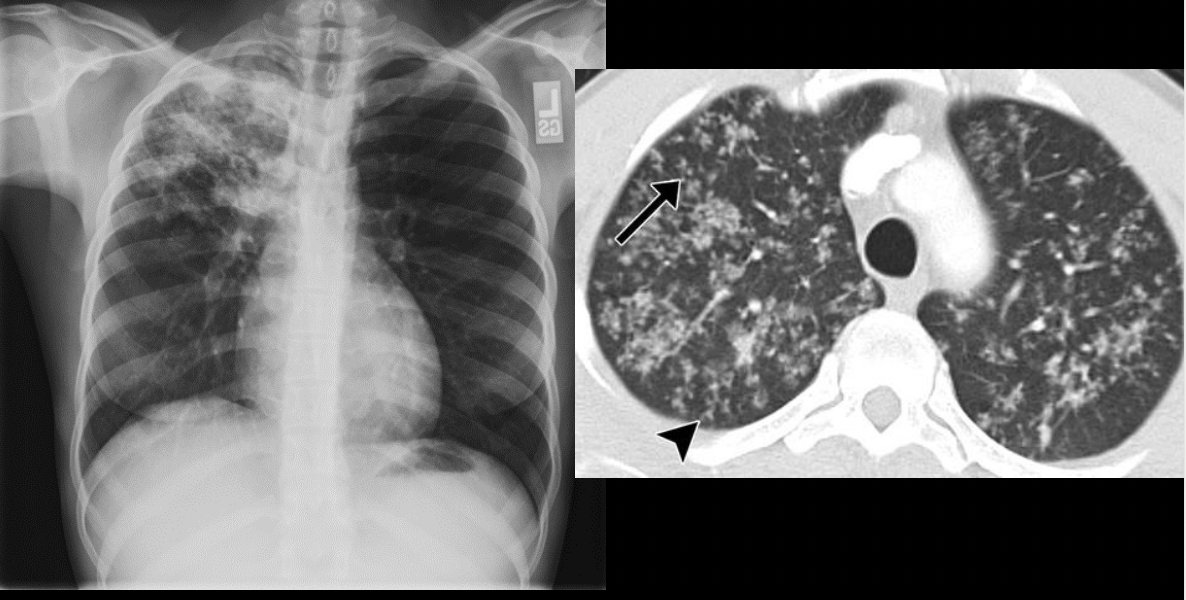

Reactivación: consolidación o parchada o cavitación

Cavitación